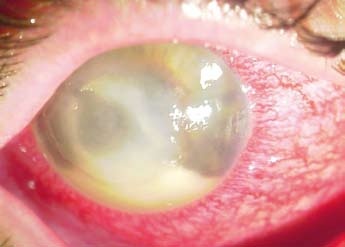

Acanthamoeba (z řec. akantha = bodlák, česky akantaméba) je rod měňavkovitých prvoků z říše Amoebozoa. Může se vyskytovat ve vzduchu, půdě, v mořské, pitné, chlorované a dokonce i zmrzlé vodě, kde se živí bakteriemi. Vyskytuje se ve dvou formách – pohyblivých trofozoitech (volně žijící a rozmnožující se vegetativní forma) nebo nepohyblivých cystách (zapouzdřená klidová forma). U člověka může způsobit dvě formy onemocnění – granulomatózní zánět mozku u osob se sníženou imunitou nebo akantamébovou keratitidu (zánět rohovky). (obr. 1)